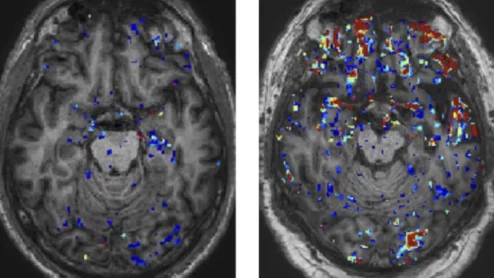

American Society of Echocardiography (ASE) President David H. Wiener, MD, FACC, FAHA, FASE, director of clinical operations at the Jefferson Heart Institute, and a clinical professor of medicine at Thomas Jefferson University, explains the growing number of multimodality cardiac imaging experts and how imaging societies need to change to meet their needs.

ASE President David Wiener detailed some of the many ways imaging societies need to adapt now that so many imagers are specializing in multiple modalities. It may be time to change how annual conferences are scheduled, for example, so that the costs of travel are easier to manage.